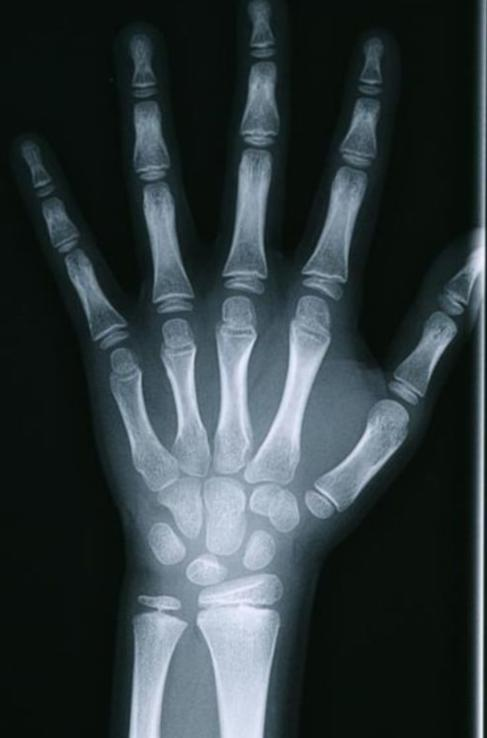

什么是骨龄片?拍摄骨龄片有什么作用?骨龄片是拍摄左手腕部的X光片。通过骨龄片,观察骨化中心出现的时间、数目、形态变化及其融合时间,判断骨骼实际发育程度,来评估生物学年龄——骨龄。

骨骺未融合的骨龄图